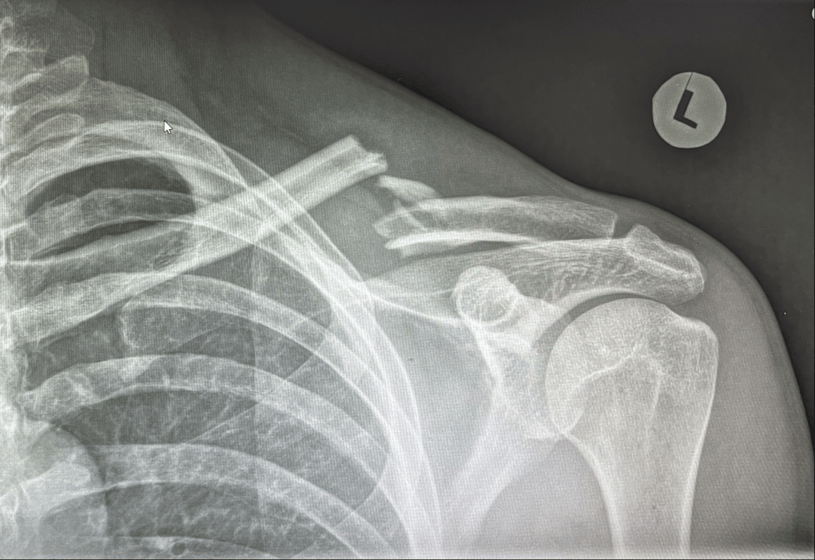

An X-ray is the primary method used to diagnose a clavicle fracture. It provides a clear image of the bone and helps the doctor determine if the fracture is displaced (misaligned) or stable.

X-ray showing a clavicle fracture with several fracture fragments and the fracture edge tenting on the overlying skin.